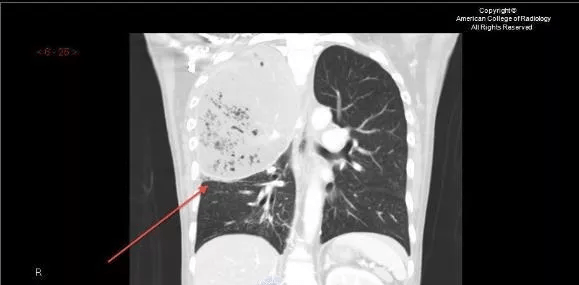

最后 , 再来回望一下 , 什么是叶间裂下坠 。

文章图片

图10-11